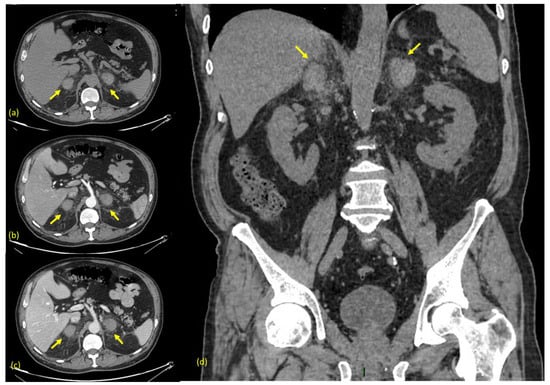

Three days after discharge, magnetic resonance imaging (MRI) was performed using a 1.5 T device, with ssFSE, LAVA, FSPGR 2D, and 3D sequences (some of which deteriorated by motion artifacts), before and after the administration of a paramagnetic contrast medium (Prohance, 0.2 mL/Kg), with a slice width between 2 and 6 mm. The MRI confirmed the enlargement of adrenal glands and showed the hyperintensity of the central adrenal region both on T1- and T2-weighted images, which is suggestive of subacute stage hematoma (>7 days to 7 weeks after onset), in association with peripheral residual parenchyma (Figure 3a–d).

Figure 3. (a) MRI axial T1 weighted. (b) MRI axial T1 weighted with fat suppression. (c) MRI axial T2 weighted. (d) MRI axial T1 weighted with fat suppression after contrast. Arrows indicate the adrenal glands. Some motion artifacts are present. The MRI performed 13 days after onset confirms an enlargement of adrenal glands with hyperintense areoles in both T1- and T2-weighted sequences, suggestive of subacute stage hematoma. After intravenous contrast, peripheral linear enhancement is observed, and it is more evident in the left gland and referred to compressed residual glandular parenchyma.

A magnetic Resonance Imaging (MRI) scan is the most accurate diagnostic modality and is considered the gold standard in follow-up. It can differentiate acute from chronic hematomas and can also ascertain the presence of an underlying tumor [20].

In the acute stage (within the first week), a hematoma has the look of an isointense or mildly hypointense mass on T1 weighted sequences, which becomes strongly hypointense on T2-weighted sequences.

In the subacute stage (between 1 to 7 weeks), it usually shows hyperintensity both on T1- and T2-weighted sequences.

Finally, in the chronic stage, (after more than 7 weeks), it typically shows a thin hypointensity edge on both T1- and T2-weighted sequences, which is correlated to hemosiderin’s presence and to the formation of a thin fibrous capsule [21].